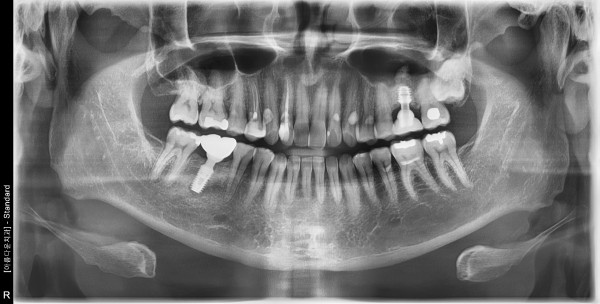

50대 남성 임플란트 식립